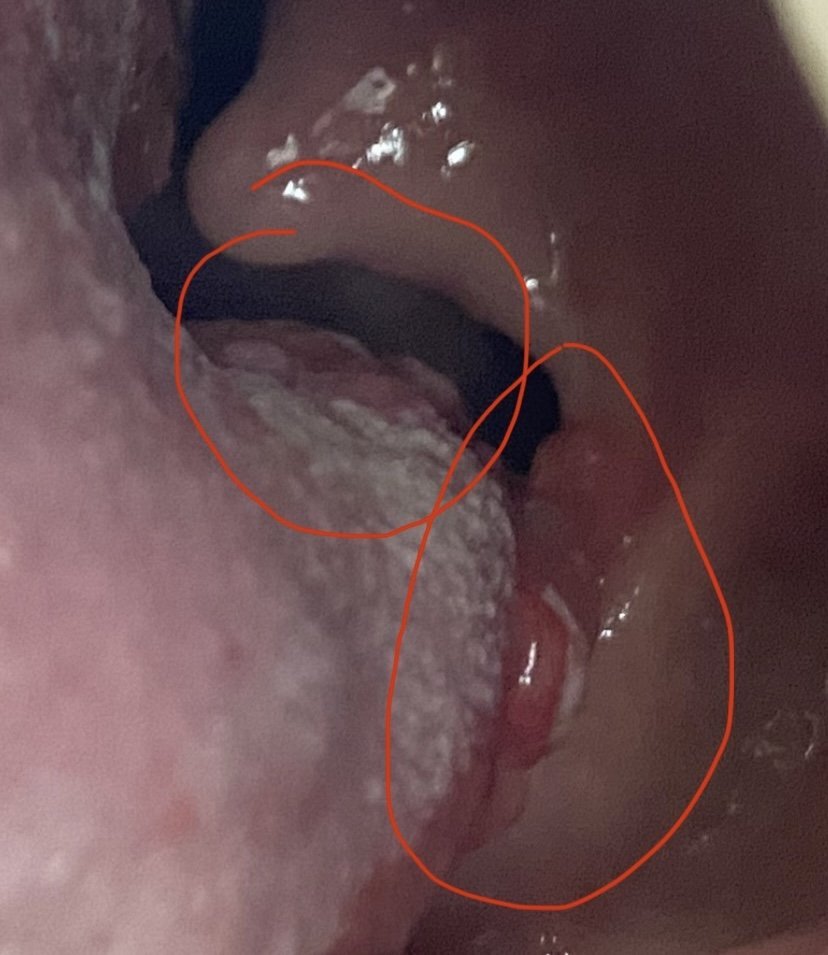

Какво е "хайри език" и как може да се подобри състоянието му?